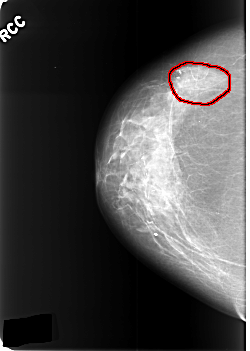

C_0391_1.RIGHT_CC

FILE: C_0391_1.RIGHT_CC.OVERLAY

TOTAL_ABNORMALITIES 1

ABNORMALITY 1

LESION_TYPE CALCIFICATION TYPE PUNCTATE DISTRIBUTION SEGMENTAL

ASSESSMENT 4

SUBTLETY 2

PATHOLOGY BENIGN

TOTAL_OUTLINES 1

BOUNDARY